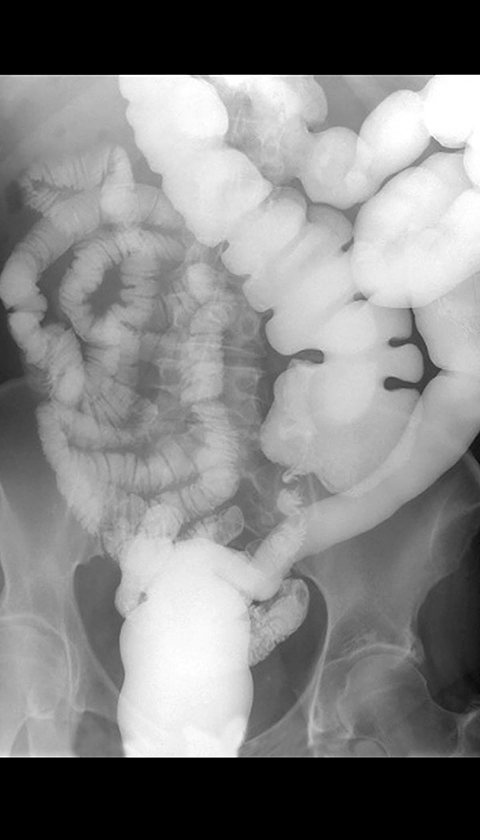

Malrotation, Barium small bowel follow through [3 of 3]